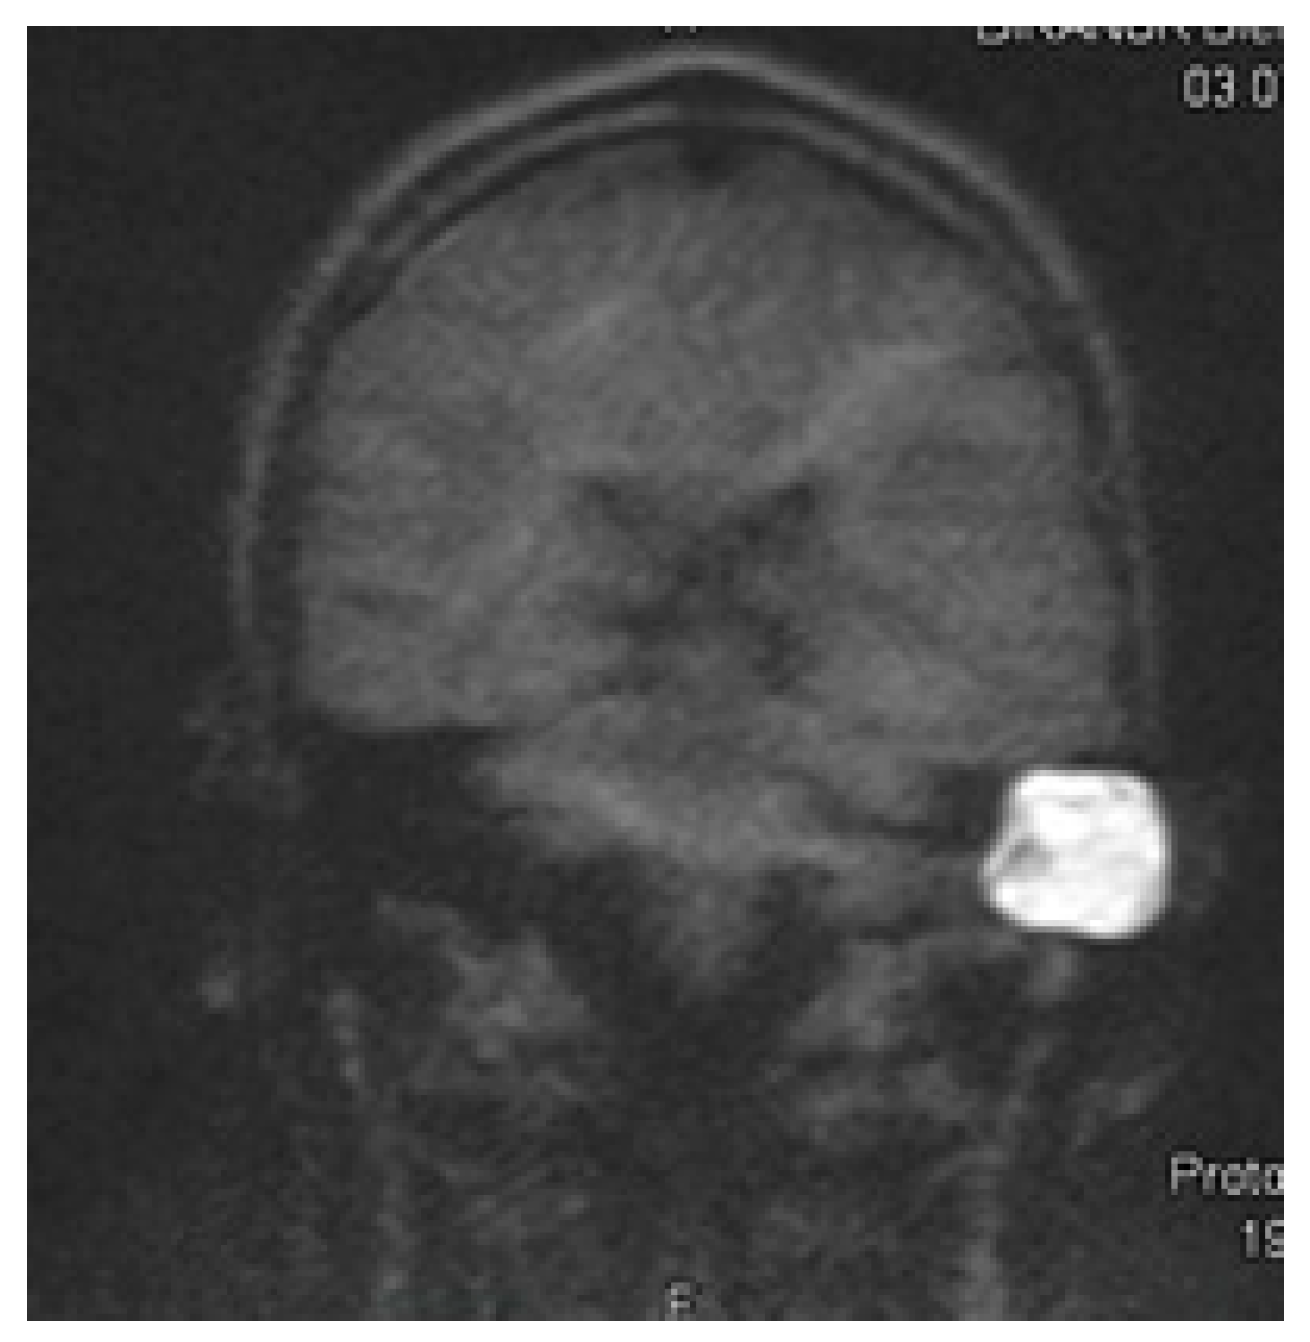

3.2. RESOLVE Sequence

3.3. HASTE Sequence